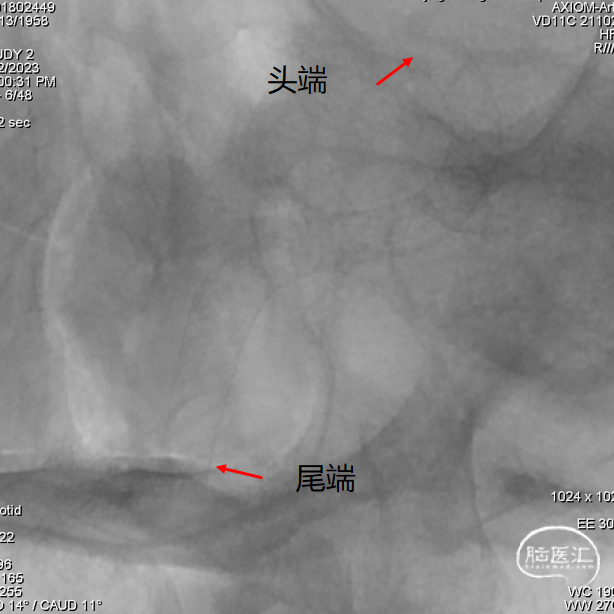

① 支架头端、尾端锚定位置的选择;

长鞘到位后工作角度造影;尽量暴露双椎汇合部,方便术中判断支架头端锚定位置。

YonFlow®血流导向密网支架头端打开顺利;通过“推拉结合”的方式打开YonFlow®后半段。

支架头端锚定位置尽量不要覆盖基底动脉近端,术中支架头端打开顺利,锚定血管壁牢靠,未出现支架头端下移和前移的情况。